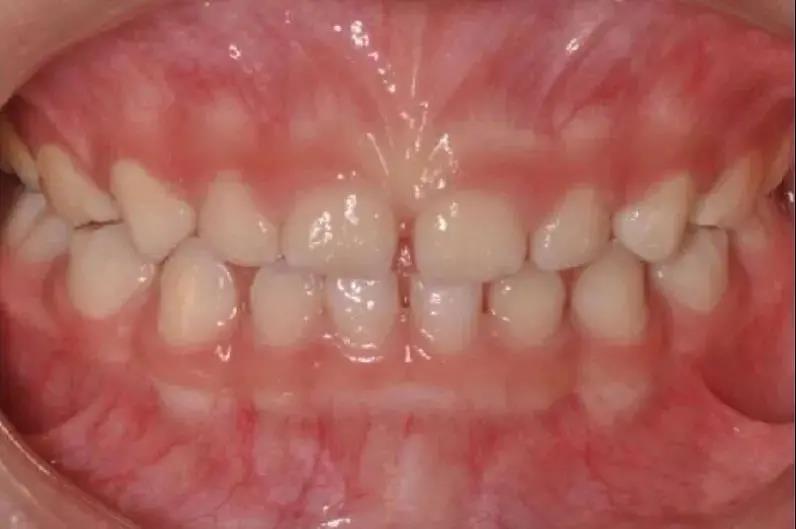

如發(fā)現(xiàn)孩子上下頜骨位置不佳

比如有明顯“齙牙”,應(yīng)盡早矯治

早期矯治可以充分利用兒童的頜骨發(fā)育潛能

調(diào)整頜骨的生長平衡及牙弓發(fā)育

因此齙牙還是要盡早診治哦